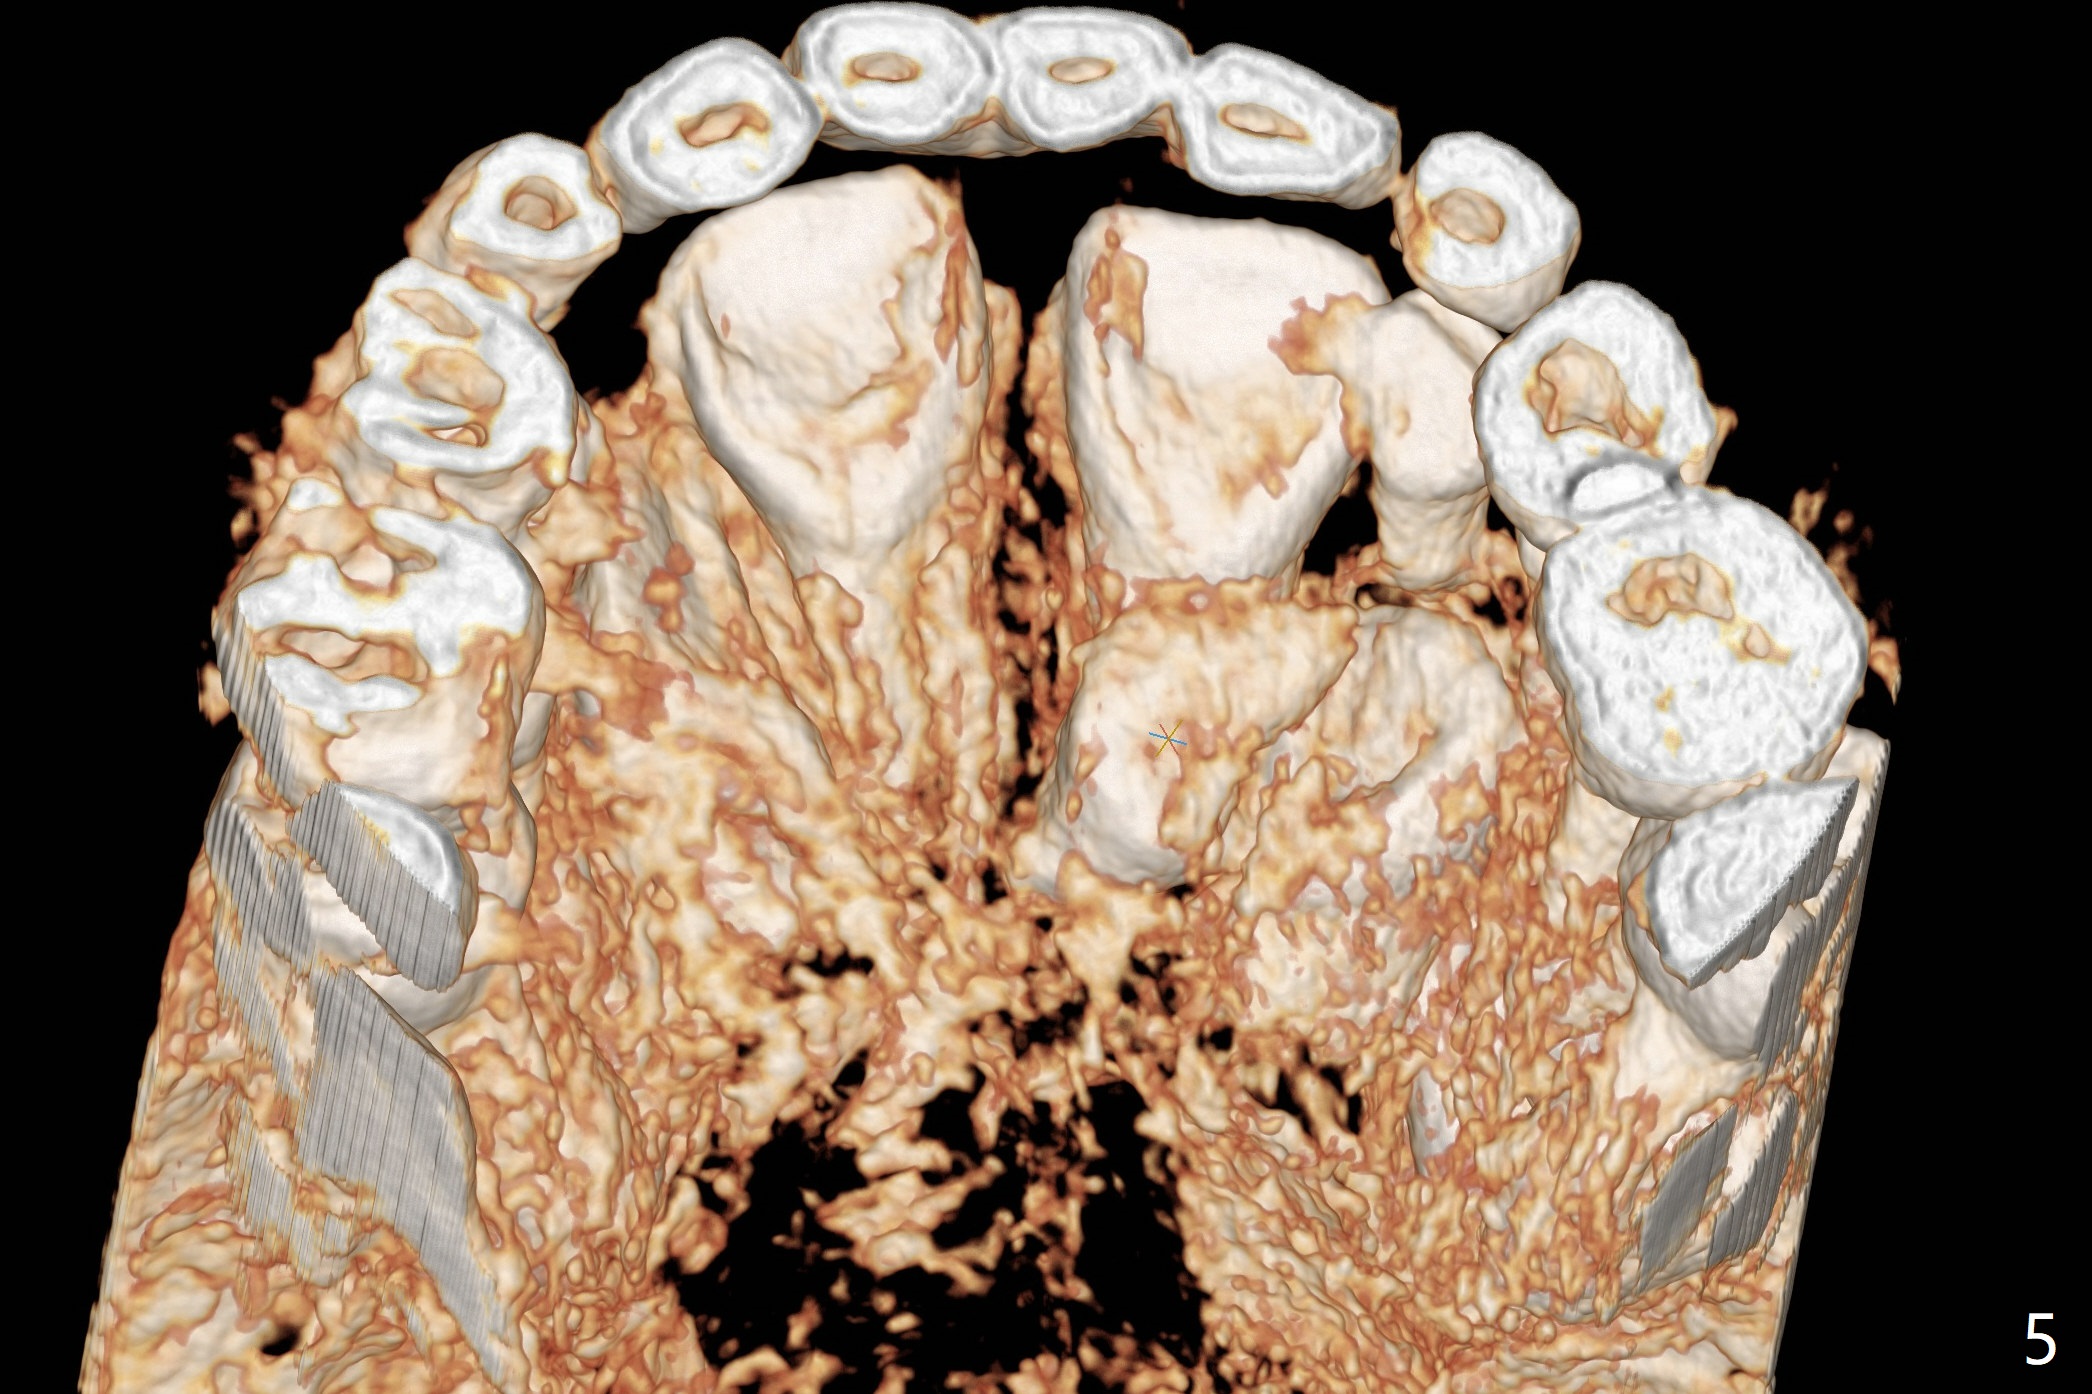

Why Are His Front Teeth Not Straight?

The father of a 7-year-old boy wonders why the upper central incisors, particularly #9, are off (Fig.1 3-D CT tooth coloring). Fig.2 (bone coloring) does not reveal much. Fig.3 (MIP, more transparent) reveals a supernumerary tooth, called mesiodens (M, an extra central incisor, abnormally shaped (cone), near the midline). Palatal view shows that the mesiodens points to the midline and distal (arrow). A palatal gingival sulcus incision will be made to expose the extra tooth (Fig.5). An elevator will be used as midline and distal as possible to avoid damage to the root of #9 and the tooth bud of #10 (Fig.6 MIP). Photos will be taken frontally and palatally preop and after incision and exposure of the mesiodens (palatal).

There is a large diastema between the upper central incisors (Fig.7). The left anterior palate is slightly elevated (Fig.8 *). In fact the cortex overlying the mesiodens (Fig. 9 *, 11 <) is to be removed with a surgical handpiece in order to extract the mesiodens (Fig.10). The left central shifts mesial in 7.5 months postop, whereas the right one remains in place (Fig.12). The tooth #7 is unerupted 1 year 4 months postop (Fig.13).